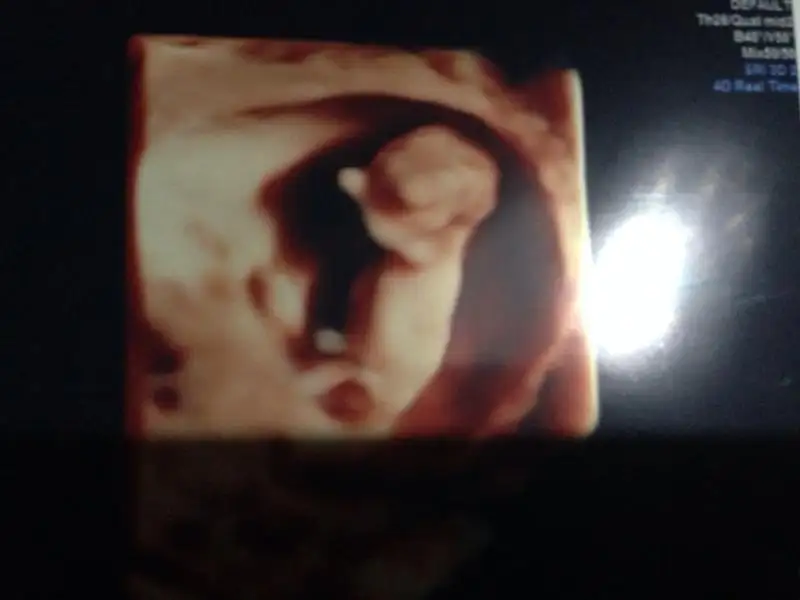

Selam kizlar 14 haftadayiz. Tahminleriniz nedir?

Bencede erkek.. en son resimde oyle gozukuyor